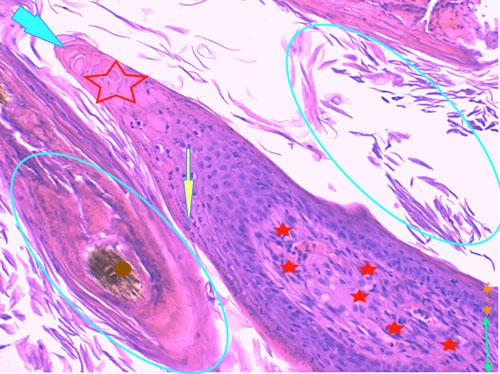

Photo 10 (Hémalun Eosine X 40) : l’épiderme et les infundibula folliculaires

sont hyperplasiques et hyperkératosiques. Des projections papillaires se forment aux marges des ostia folliculaires.

Le derme montre une inflammation péri-vasculaire.

Légendes de la Photo 10 :

- Double flèche bleue : couche cornée hyperkératosique

- Double flèche orange : épiderme (portion non kératinisée)

- Double flèche verte : derme

- Ronds marrons : tiges pilaires

- Flèches jaunes : projections papillaires de l’épiderme hyperplasique se formant aux marges des ostia folliculaires

- Étoiles rouges vides : follicules pileux, infundibula hyperkératosiques (orthokératose)

- Étoiles rouges pleins : infiltrat dermique périvasculaire